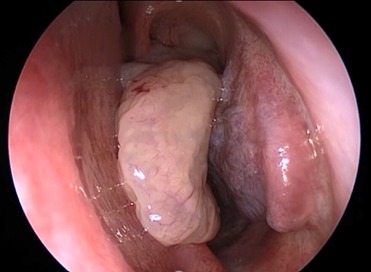

- Nasal polyps

- Nasal endoscopy

Advanced Treatment – FESS

For chronic or recurrent sinusitis not responding to medicines, Aram Advanced Healthcare, Puducherry offers Endoscopic Sinus Surgery (FESS) – a minimally invasive, camera-guided procedure to clear blocked sinuses and restore normal drainage.

- High-definition endoscope for precision